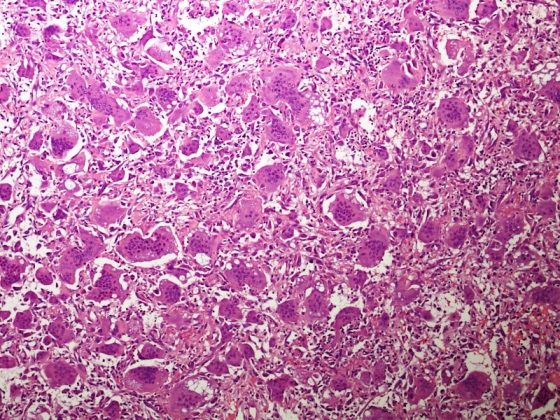

Microscopic (histologic) description

- Lobular pattern composed of groups and clusters of osteoclast-like multinucleated giant cells

- Vascular fibroblastic stroma

- Hemorrhage and hemosiderin deposits

- Tunneling resorption of adjacent uninvolved bone (J Int Oral Health 2015;7:50)

Microscopic (histologic) images

A 49 year old hypertensive and diabetic man presents with a complaint of right mandibular pain, swelling and intraoral bleeding for a period of 12 months. There was a gradual increase in size and pain. Xray revealed a well defined multilocular lesion within the right mandible. Incisional biopsy was performed and microscopic examination revealed a lesion in the given photomicrograph. What is the most likely underlying etiology?

D. End stage renal disease. The photomicrograph shows a lesion composed of scattered osteoclast-like giant cells in a vascularized spindled stroma characteristic of brown tumor of hyperparathyroidism. End stage renal disease causes decreased glomerular filtration due to reduced nephron function, which results in decreased synthesis of 1,25 dihydroxyvitamin D3 by the kidney. This leads to decreased absorption of calcium by the gut. Consequently, there is an increased level of serum phosphate. Increased serum phosphate causes serum calcium to be deposited in bone, also leading to a decreased serum calcium. In response to low serum calcium levels, the parathyroid glands secrete increased parathyroid hormone, which results in secondary hyperparathyroidism.